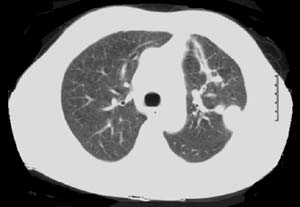

When an isolated pulmonary nodule is lying deep to a flat surface of the lung, VATS wedge resection using the conventional endoscopic staple-cutter is often technically difficult. Even if this could be done, it usually sacrifices more functional lung tissue than would be necessary or desirable. This could have a major impact on the recovery of patients who are elderly, frail with multiple co-morbidities, and borderline lung function. It is for this group of patients that new technological approaches may offer an advantage. Patients with peripheral pulmonary nodules for diagnostic or therapeutic wedge resection are suitable candidates to consider. The nodule should ideally be located in the peripheral one-third of the lung, and should be less than 3cm in maximal diameter (Figure 1).